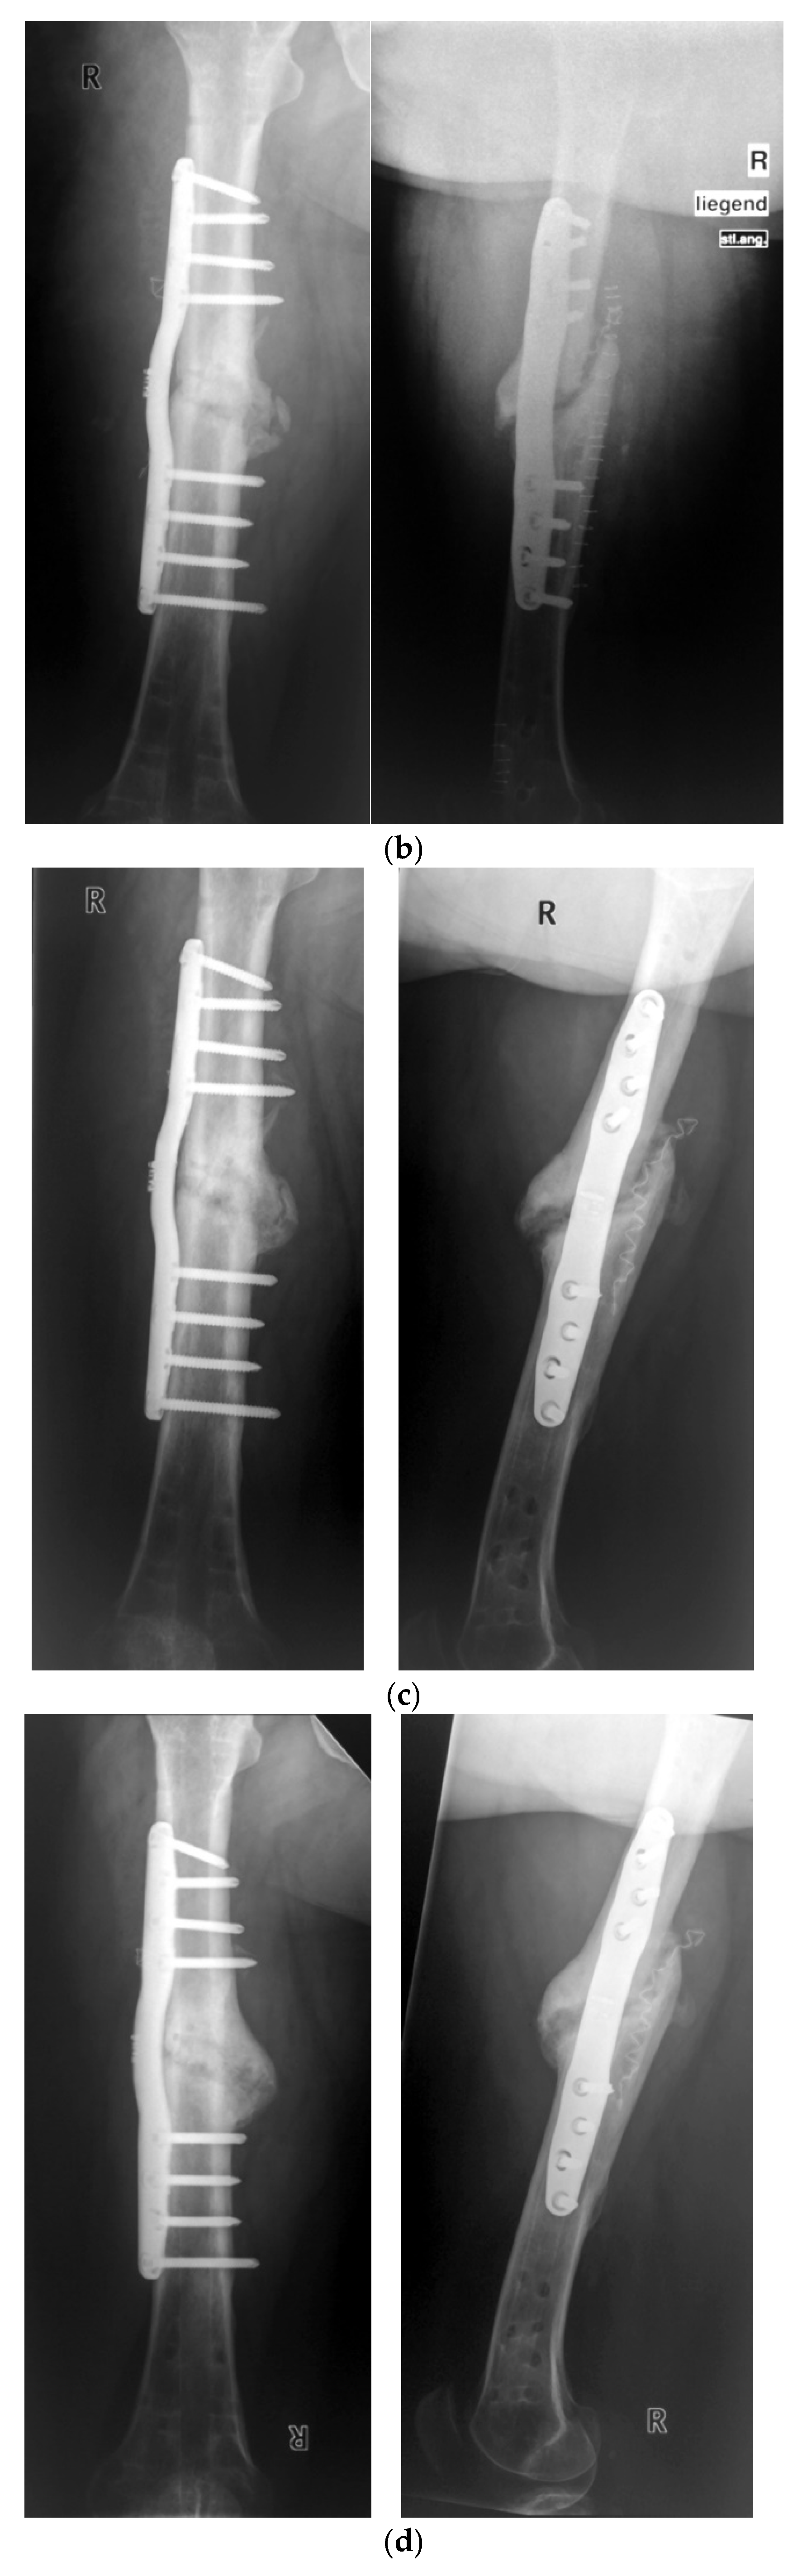

- Seide, K.; Aljudaibi, M.; Weinrich, N.; Kowald, B.; Jürgens, C.; Müller, J.; Faschingbauer, M. Telemetric assessment of bone healing with an instrumented internal fixator. J. Bone Jt. Trauma Surg. 2012, 94-B, 398–404. [Google Scholar] [CrossRef]

- Kowald, B.; Seide, K.; Auerswald, M.; Faschingbauer, M. Slow-healing non-unions. Measurement of mechanical stability with the instrumented implant. 3 case reports. Trauma Berufskrankh. 2019, 21, 181–192. [Google Scholar] [CrossRef]

- Faschingbauer, M.; Seide, K.; Aljudaibi, M.; Kowald, B.; Münch, M.; Weinrich, N.; Jürgens, C.; Moss, C.; Kirchner, R. Intelligent implants for monitoring bone healing. Trauma Occup. Dis. 2013, 15, 240–248. [Google Scholar]

- Kienast, B.; Kowald, B.; Seide, K.; Aljudaibi, M.; Muench, M.; Faschingbauer, M.; Juergens, C.; Gille, J. An electronically instrumented internal fixator for the assessment of bone healing. Bone Jt. Res. 2016, 5, 191–197. [Google Scholar] [CrossRef]